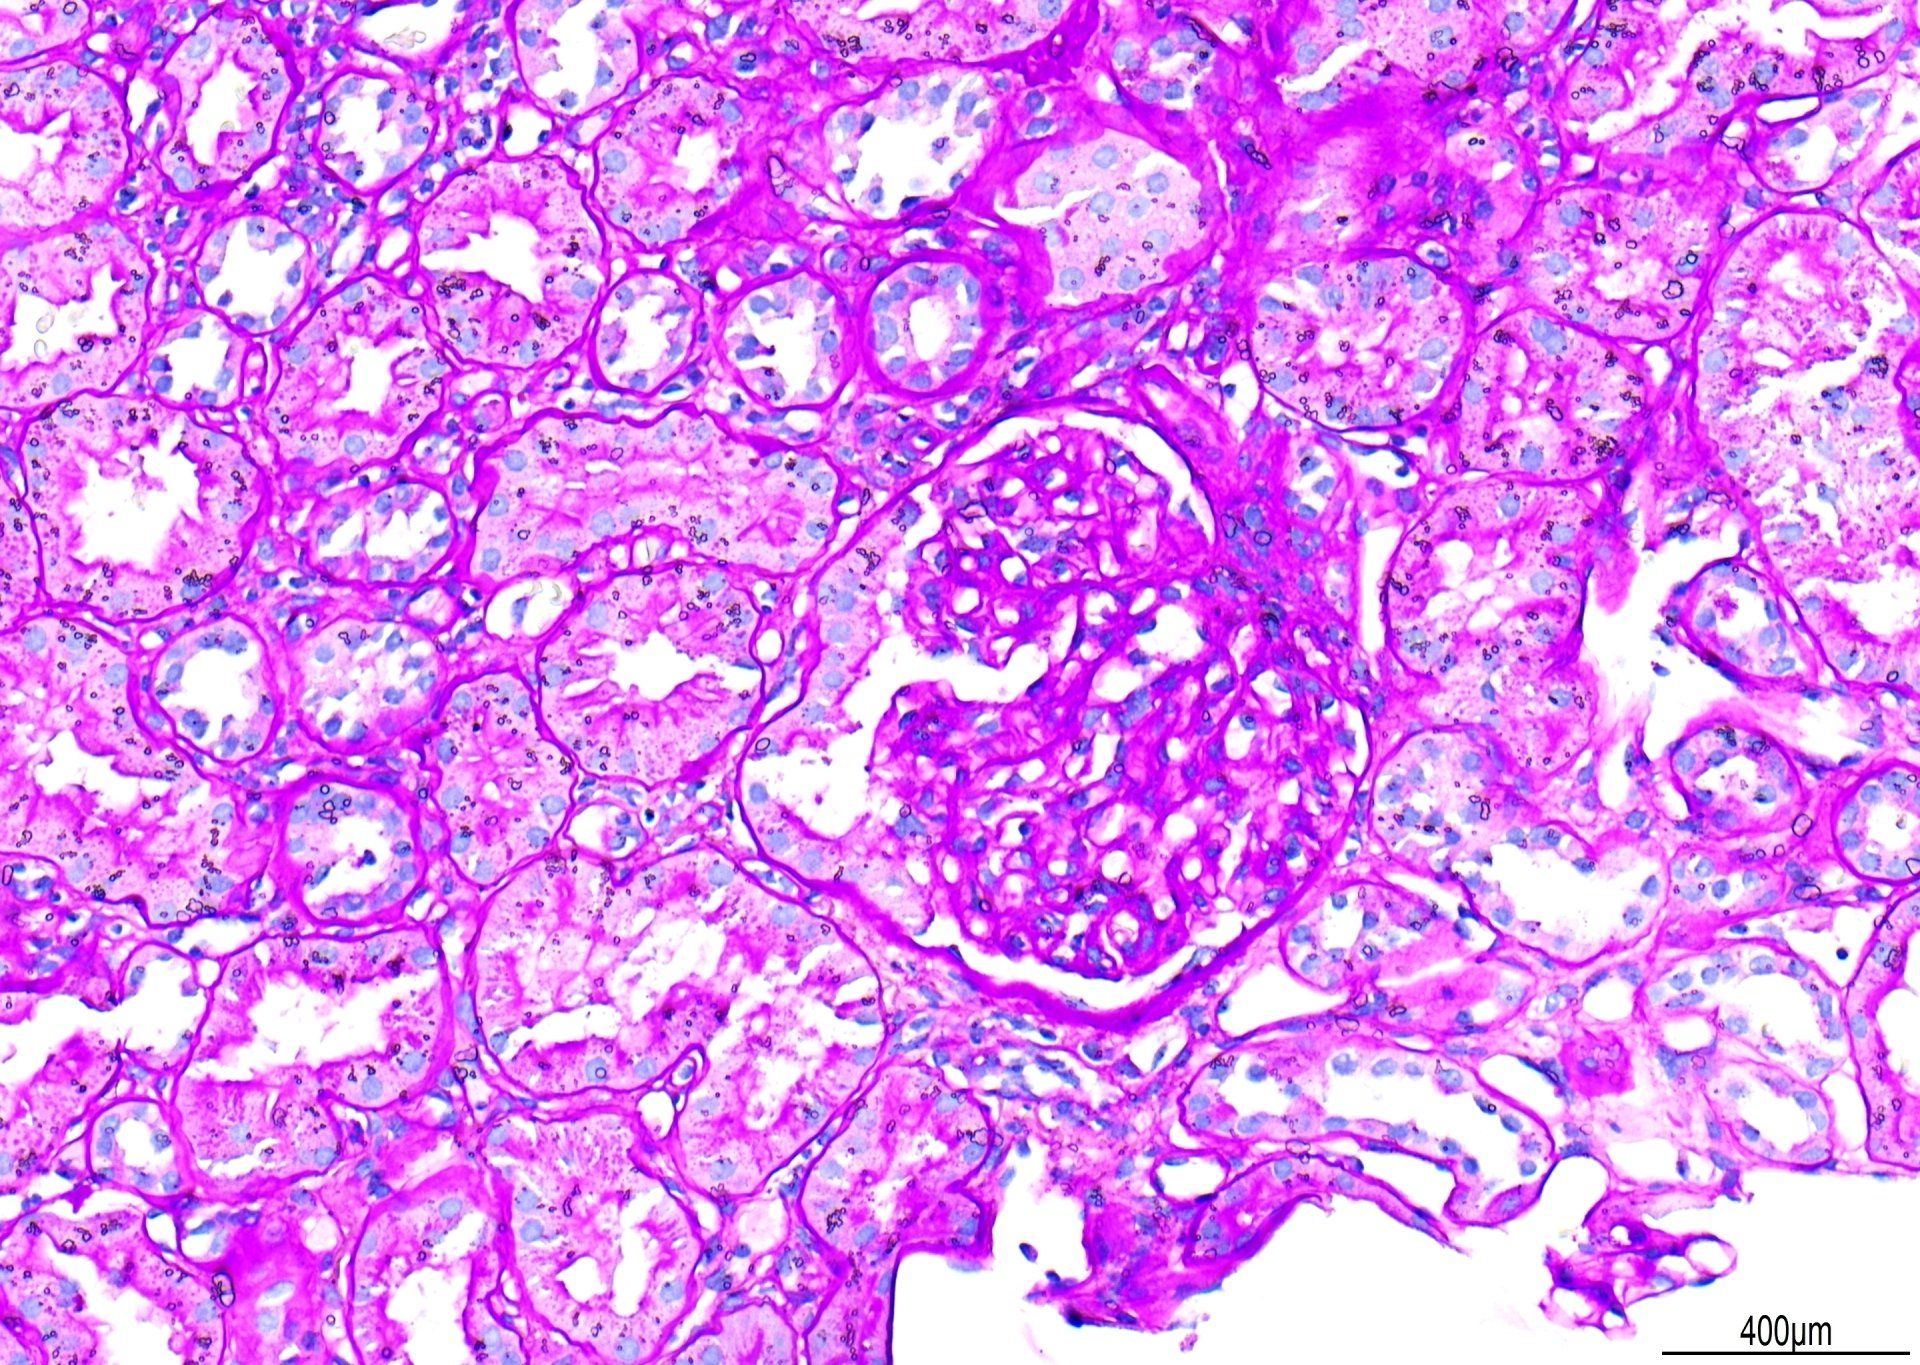

PAS - Nierregeling

Gezien bij x20 is dit een voorbeeld van een PAS-kleuring. Er werden punten afgetrokken voor 'primaire achtergrondkleuring'. Hoewel de glomerulaire basale membranen goed gekleurd zijn, zou het contrast beter kunnen zijn met minder Schiff-achtergrondkleuring. Daarnaast waren er waterdruppels onder het dekglaasje te zien. De totaalscore voor deze sectie was 7/10.